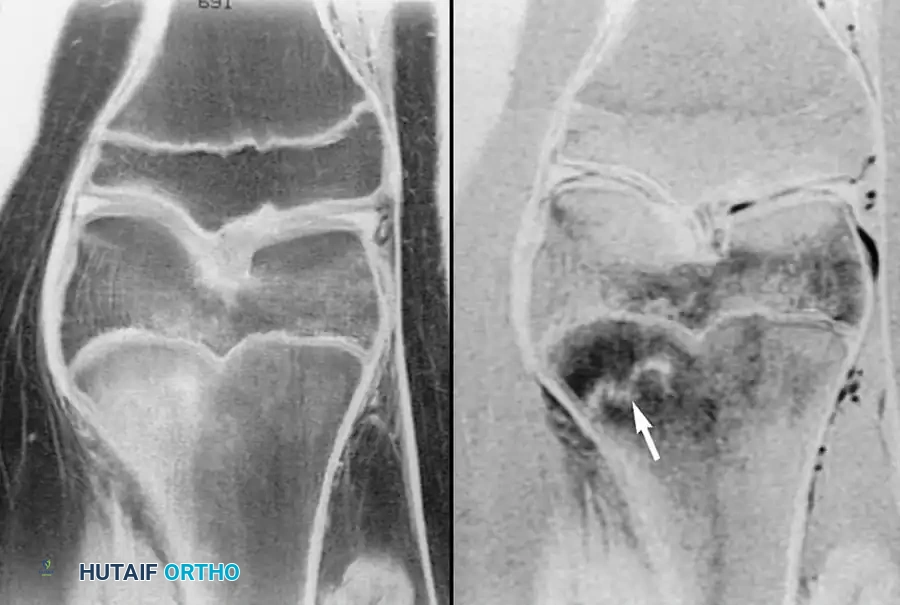

لا تقتصر قوة الرنين المغناطيسي على مفصل الورك فحسب، بل تمتد لتشمل المفاصل الأخرى كالركبة، مما يثبت فعالية هذه التقنية في كشف أدق التفاصيل التشريحية والمرضية في العظام والغضاريف. نستعرض هنا بعض الأمثلة التي توضح دقة الرنين المغناطيسي في تشخيص إصابات المفاصل:

هذه الصور تؤكد بما لا يدع مجالا للشك أن الاعتماد على الرنين المغناطيسي يوفر خريطة طريق واضحة للطبيب المعالج، سواء كان يتعامل مع كيس زلالي، أو كدمة عظمية، أو كسر خفي في صفيحة النمو، أو آفة غضروفية، مما ينعكس إيجابا على دقة التشخيص في مفصل الورك والمفاصل الأخرى.